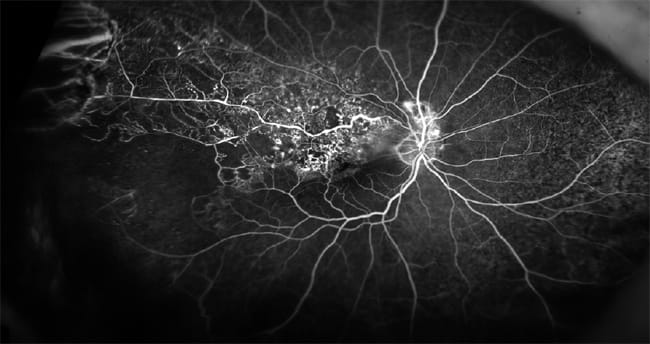

Figure 1. Hydroxychloroquine toxicity with “bull's eye” maculopathy and peripheral pigmentary changes that have never been described before in the literature.